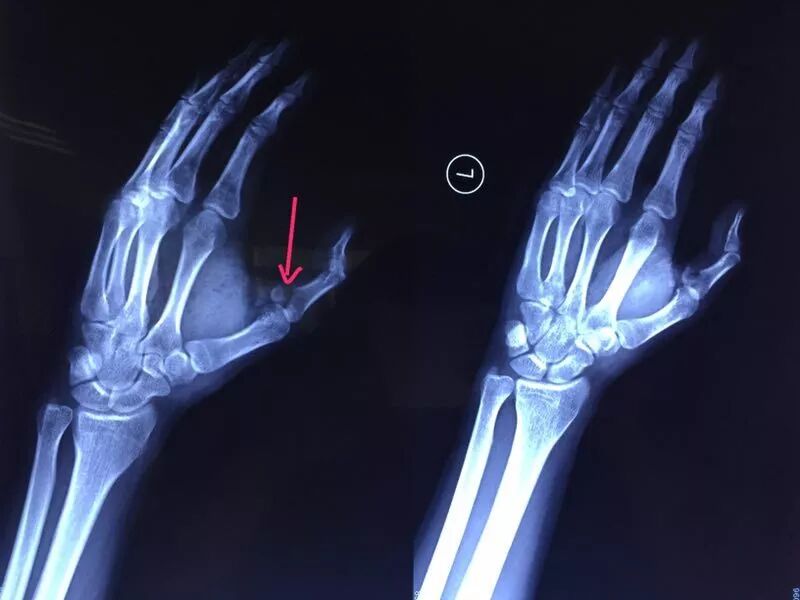

小袁发出惨叫,家人闻讯赶来,只见他左手动弹不得,伤口血流不止。他随即被送到省人民医院就诊。X光检查发现,小袁左手拇指近节指骨骨折,需手术固定。

医生为小袁进行骨折复位内固定手术

当晚,医院为小袁进行手术,两小时手术顺利完成。术后,小袁的左手还需采用石膏固定4~6周。